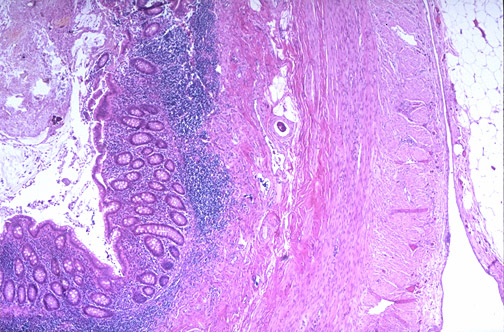

1.5 TISSUE STAINING

REQUIREMENTS PRINCIPLE

Materials Reagents The principle of tissue staining is to enhance the

important features or part of the tissue. In tissue

Unstained tissue slides Hematoxylin 3G (Sakura) staining of histopathology, hematoxylin and eosin

Eosin (Sakura) the dye is routinely used. Hematoxylin 3G is a basic

Xylene dye that is usually used to stain the nucleus

Apparatus Alcohol (Absolute, 95%) components of the tissue and give the bluish

Slide racks Distilled water colour. On the other hand, eosin is used to stain

Forceps Tap water cytoplasmic components of the tissue and give rise

Filter paper to a pinkish color.

PROBLEM REASON SOLUTION CONCLUSION

The hematoxylin stain The efficacy of Discard the hematoxylin and Good tissue staining and reagent

is too light. (The nuclei hematoxylin is reduced. replace with new hematoxylin. preparation skills were able to be

are too pale) achieved in the third and fourth cycles.

The section is too thick. Recut the section with Although all the prepared slides were

The hematoxylin is too appropriate thickness. stained according to the given standard

dark. (The nuclei are The section is too thin. operating procedure, some tissues

overstained). Recut the section if required sample has a darker color than the other

after checking the thickness of tissues. This shows that tissue staining

The eosin is too pale. the section. are also affected by the thickness of the

tissues.

Cytoplasm is The section have been Decrease the staining time.

overstained and has stained in eosin for too Allow more time for

poor differentiation. long. appropriate dehydration with

The section dehydrated in alcohol.

alcohol too fast.